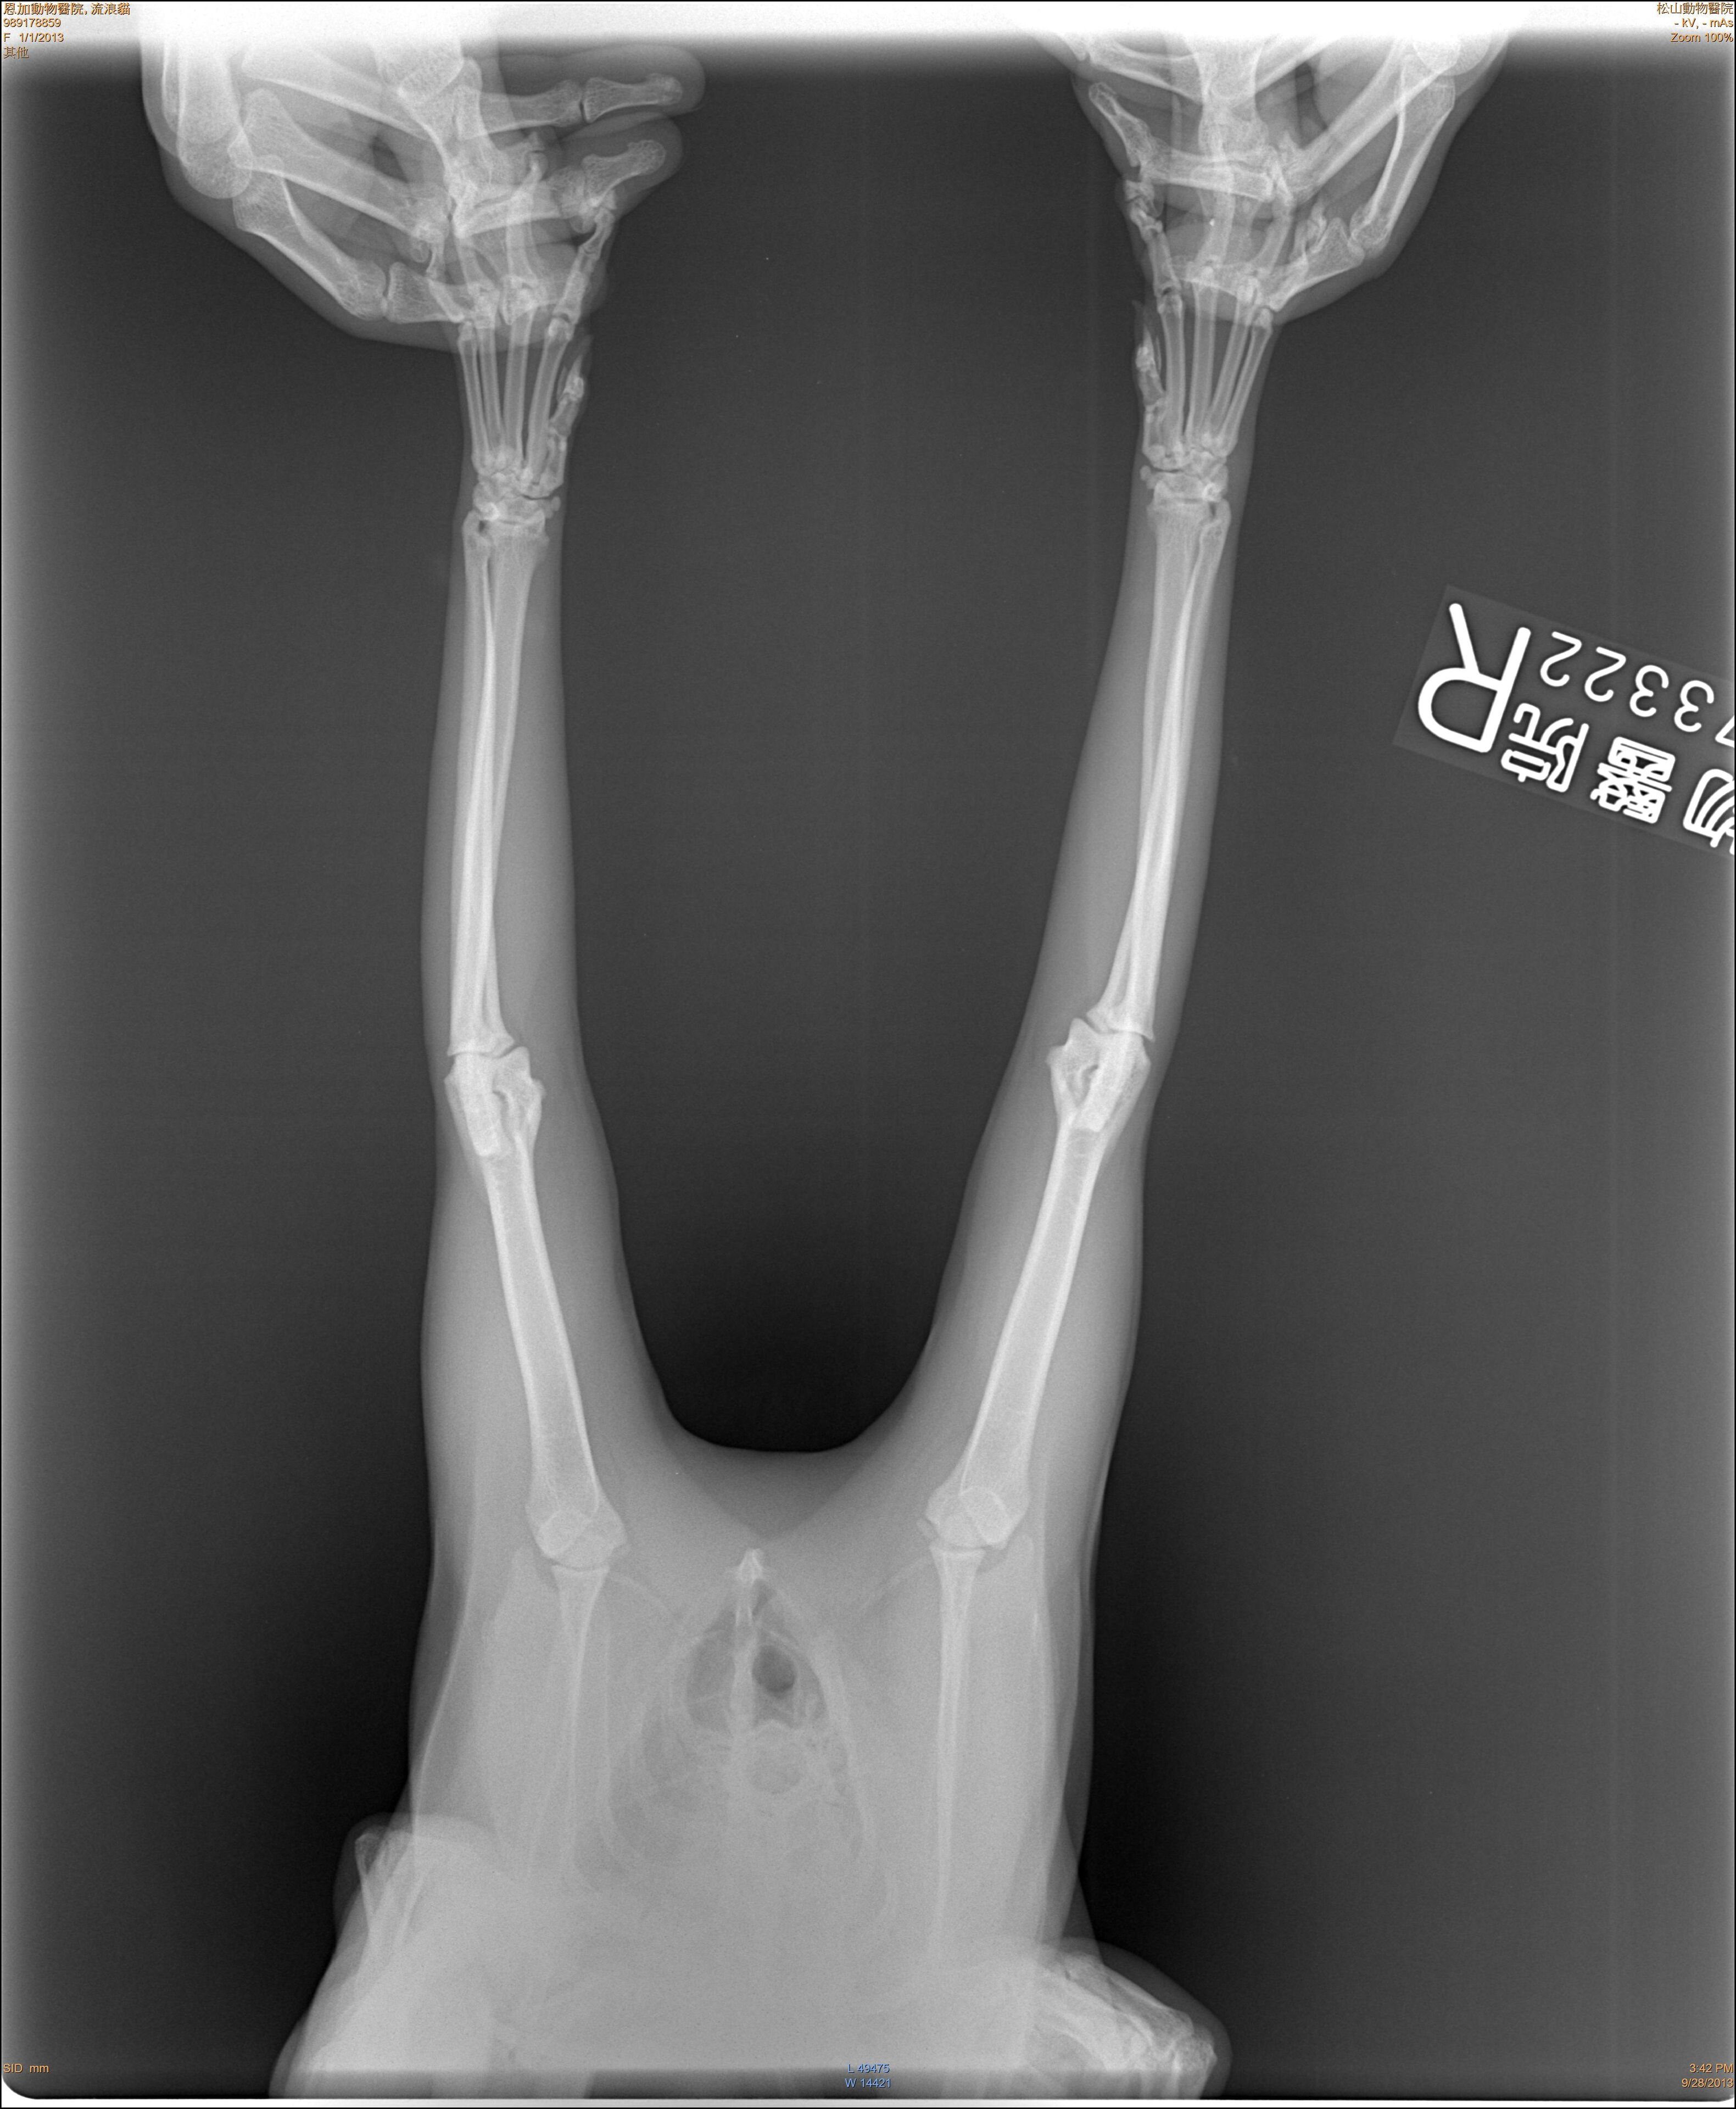

主題: 左前肢折斷的半橘猫 申請者姓名: 陳怡靜 花色: 申請日期: 2013-10-08 17:02:47 申請者部落格: 申請者臉書網址: 所在縣市/合作醫院: 台北市/恩加動物醫院 治療費用: 2500元 需求人數: 6人 已結案 (2014-01-10 17:58:16) 報名人員: clement(已付款)、Forest(已付款)、林醟鉗 x2(已付款)、Lulu Hsieh(已付款)、Anita Yin(已付款)、 候補人員: 動物病情說明: 這隻半橘街貓已餵養有五年已上的時間,平常每天都會出現要飯飯吃,連颱風天也會在車下等,昨天餵食食沒看到牠就覺得奇怪,很擔心!結果在更晚時去找牠喊了好久,才看到牠一跳一跳的出來,前腳有一隻是折的。便趕快將牠抓起來,抓了好久不進籠,最後用網子順利捕到,於今早送醫治療。